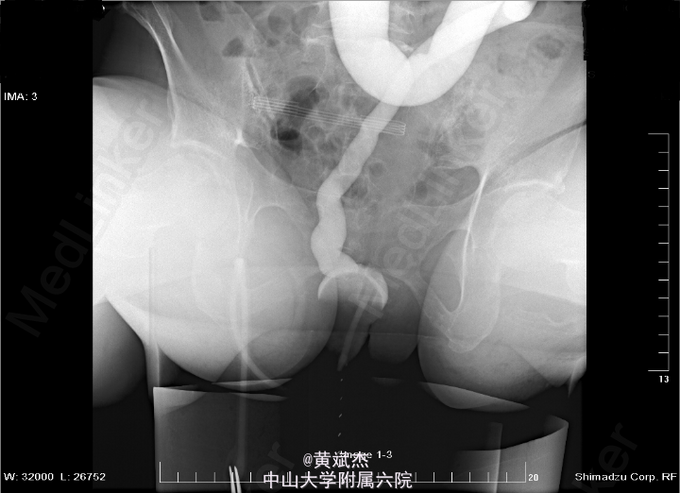

女,59岁,因“直肠癌术后3年余,造口脱垂2年余”入院。3年前因直肠癌行DIXON术,病理示T2N1M0。术后曾出现失血性休克,曾行剖腹探查+吻合口缝扎止血+横结肠造瘘术。共行化疗6程(1程:奥沙利铂+5-FU;2~6程:伊立替康+5-FU),放疗25次(50Gy/25F)。2年前造口反复轻度脱垂,渐加重。

体查:上腹部见横结肠单腔造口,轻度脱垂,造口通畅,肛门指检:肛周未见肿物脱出,进指4cm可触及吻合口通畅无狭窄,直肠粘膜光滑,未及肿物,指套退出无血染。心肺腹余无特殊。 辅查:排粪造影正常。肛门测压:收缩功能良好,吻合口稍窄,直肠粘膜感觉及抑制反射未完成。盆腔MRI:1、直肠癌术后2、直肠呈铅管样改变,考虑放射性肠炎治疗后改变,请结合内镜。3、子宫多个肌壁间肌瘤。肠镜:进镜20厘米肠腔缩窄,黏膜质脆接触易出血。造口进镜30厘米,肠腔较多粪便,距造口约5厘米见一直径约0.5厘米息肉。

目前诊断: 1、放射性肠炎? 2、造口脱垂 3、直肠癌术后放化疗后 4、子宫肌壁间肌瘤 治疗:暂不关闭瘘口、坐浴、软化大便、抗炎、营养支持等对症治疗。